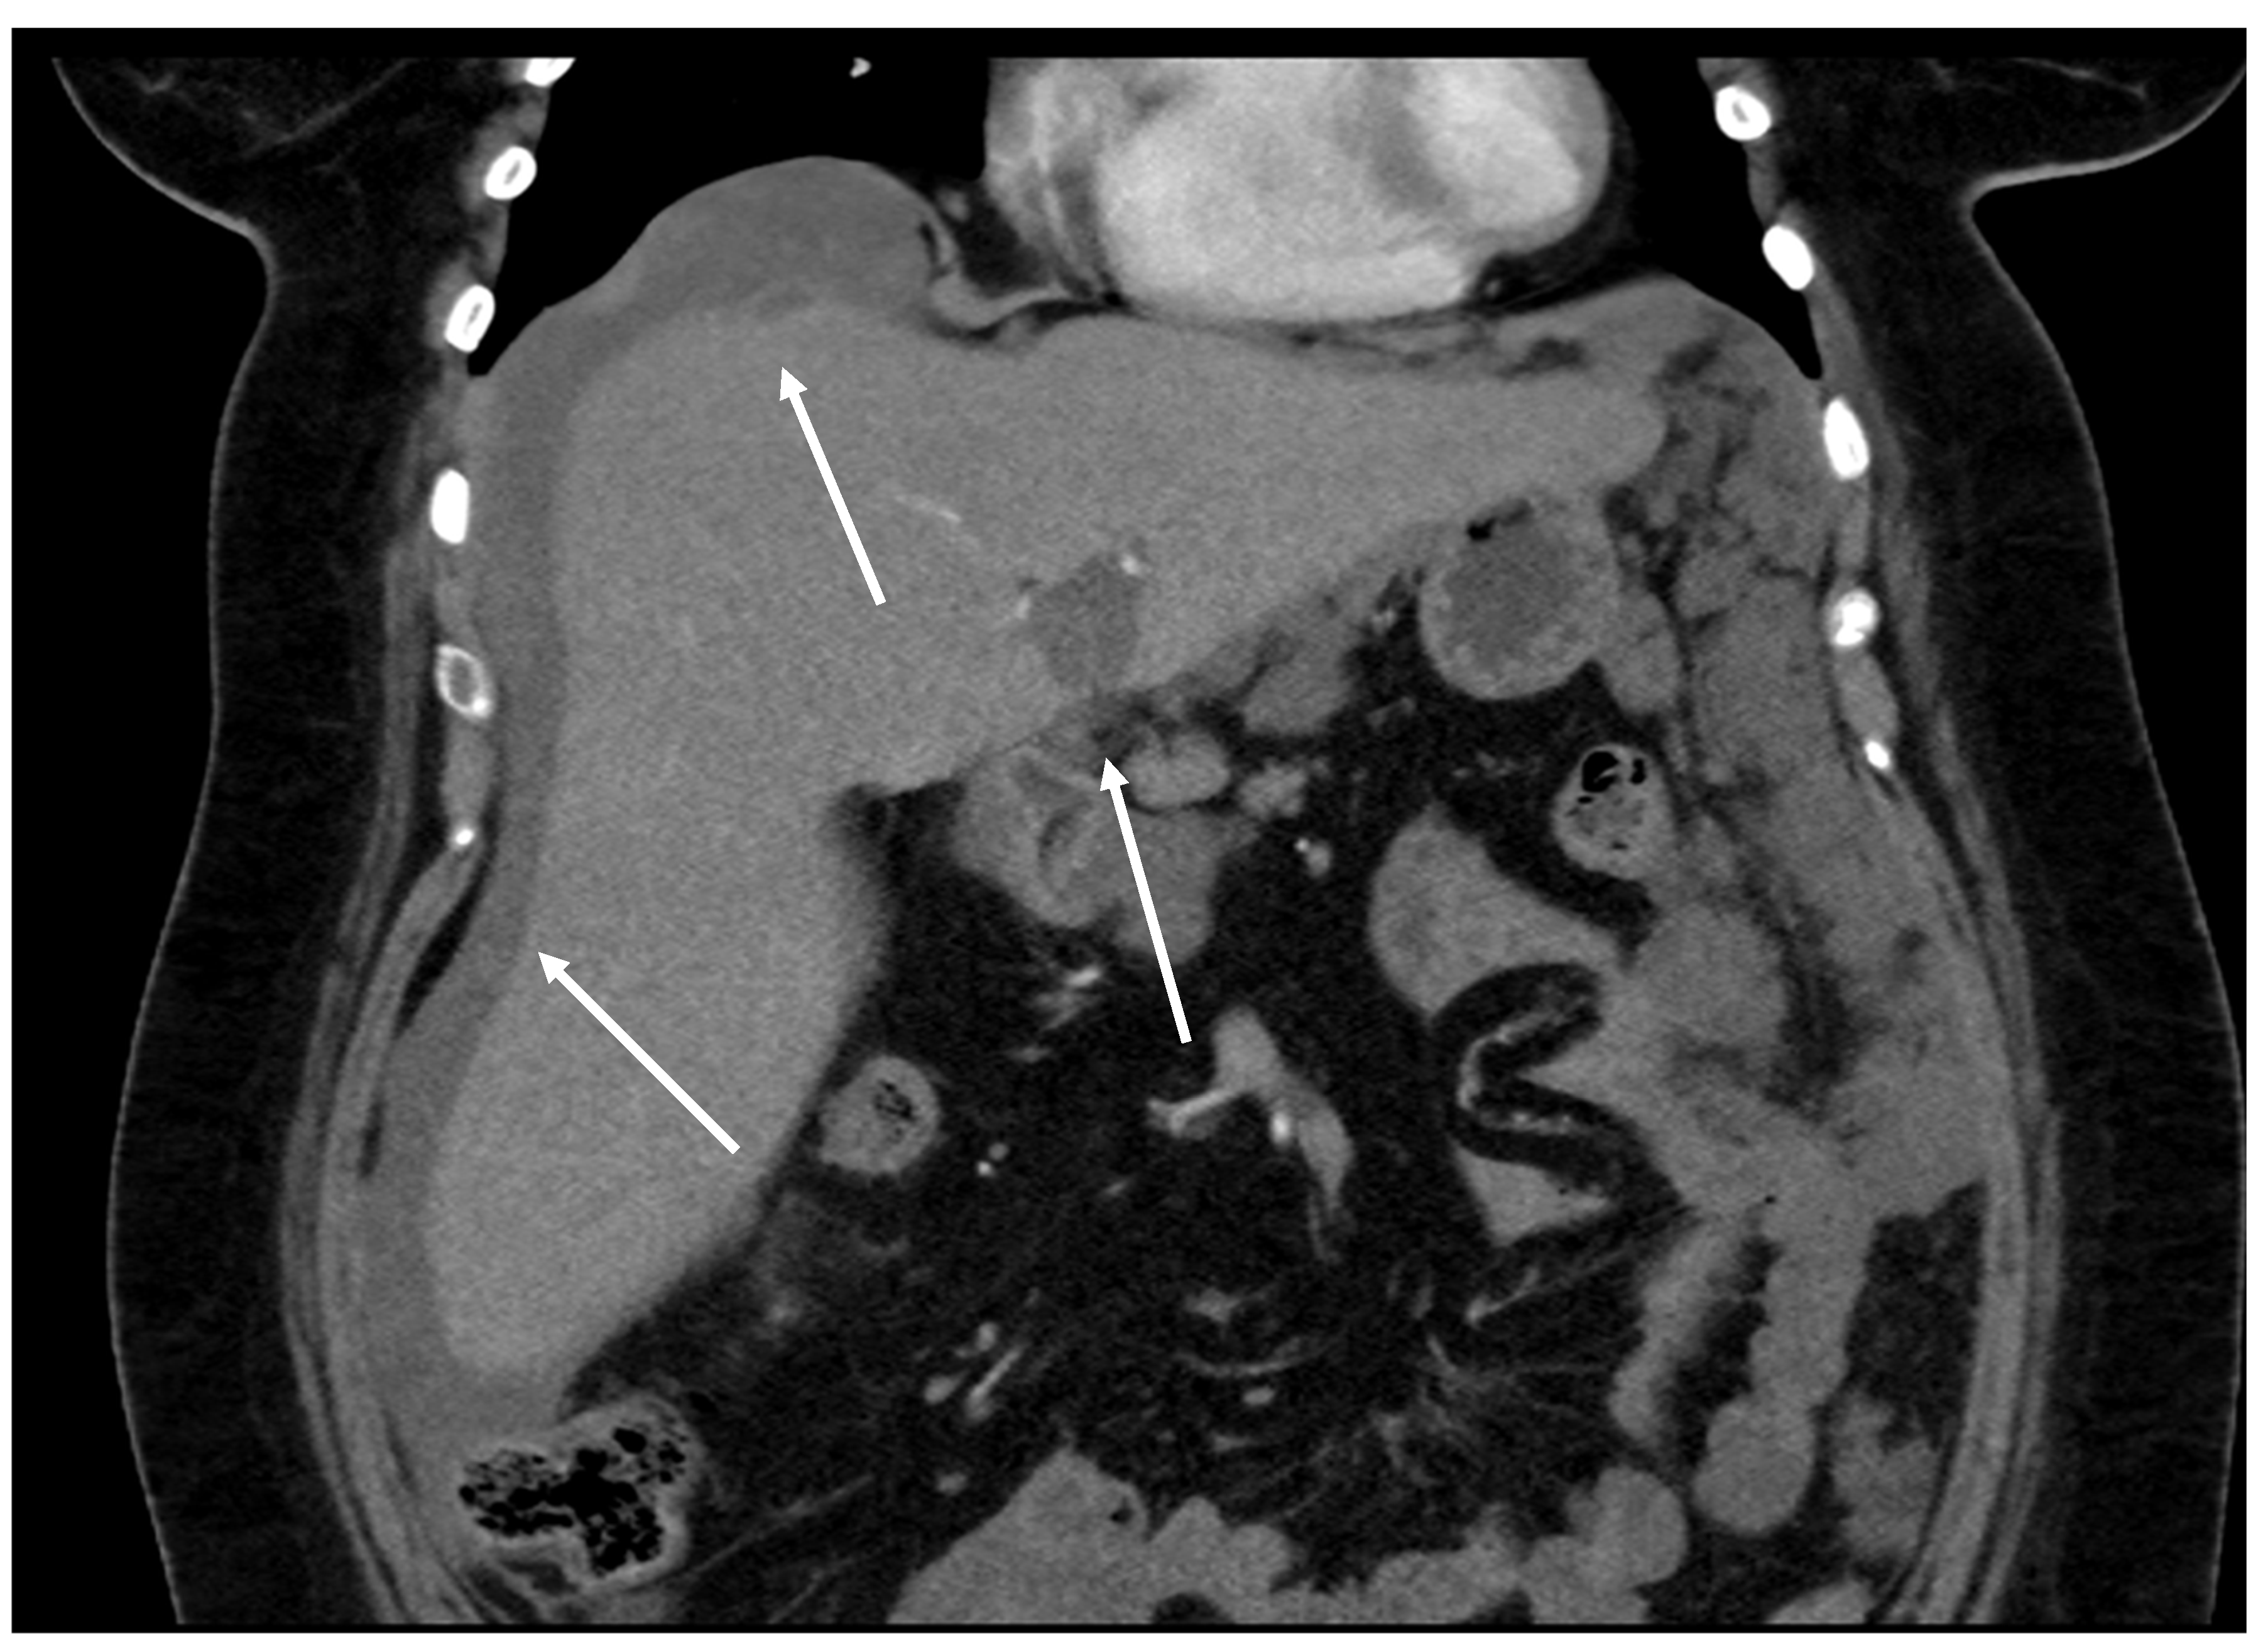

Figure 12. CT, venous phase, coronar plane.

Figure 11, Figure 12, Figure 13, Figure 14 and Figure 15. Advanced stage of the disease. The abdomen is full of tumors and mucin. Typical signs are heterogeneous or hypodense masses in the form of lobules often with septa, which could be enhanced by contrast and could be associated with calcifications.

Patients with a misdiagnosed rupture of the mucocele may develop pseudomyxoma peritonei. It is characterized by the presence of an abundant gelatinous substance in the abdomen. Diffuse, progressive, and abundant mucin-containing tumor cells are typical of this disease [2] (Figure 11, Figure 12, Figure 13, Figure 14, Figure 15 and Figure 16). The interval between rupture and advanced disease is several years. In our clinical series, the interval was about 5 years. In the literature, we found a wide range of this interval from 12 months to 10 years [9,10]. The natural history of PMP revolves around the “redistribution phenomenon”, whereby mucinous tumor cells accumulate in the Douglas pouch, in the diaphragm (more on the right), and the small and large omentum (Figure 17). The small intestine is less involved [4]. Pseudomyxoma peritonei is a slowly progressing disease, which fills the peritoneal cavity over time. There are several classifications of pseudomyxoma. The most commonly used is the PSOGI classification [2]. Mucinous accumulation progresses to malnutrition, bowel obstruction, and respiratory compromise. Rarely, the tumor may spread to the pleural cavity. This has been described in 5.4% of cases. It may occur spontaneously or as a result of diaphragmatic injury during cytoreduction [8,11].